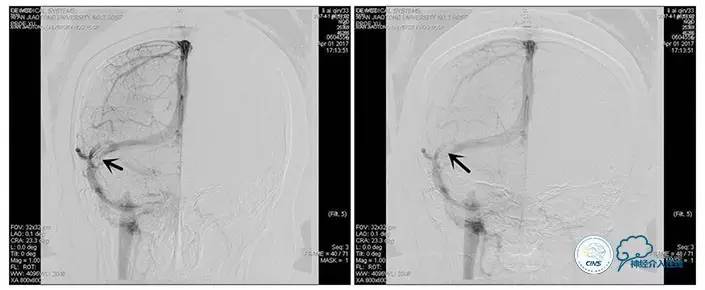

术中造影

5ml/s,总量8ml,压力100~150

手术方案

1、6mm×20mmAviator球囊(Cordis)分段对狭窄部位进行扩张。

2、植入7mm×40mmPrecise自膨支架。